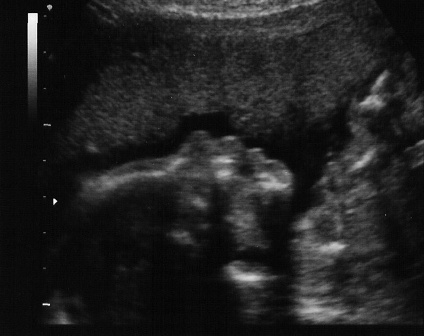

Ilyen képeket kaptam...

Gigi ezeket a képeket eddig nem mutattad meg???? :shock:

Gigi nagyon nagyon cuki a baba, szinte megszólal,és mikor csinálták, most a 21. héten?nekem azt mondták, a 24.-28. héten menjek, mert még túl vékony a baba most.